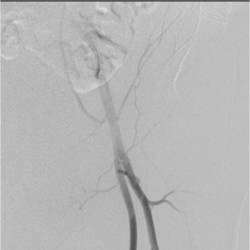

Gallery of Unlabled Radiographs from Lecture (Dr. French) - 2020

Click a thumbnail to enter the gallery display. Click the file name link at the bottom left of the gallery display to view the image at high resolution.

Labeled Plates from Lecture (Dr. French) - 2020

RadiologyLowerLimbThoraxQuestionPoolLabeled_01_2020.pdf

Click right side of plate to step forward or left side of plate to step backward.